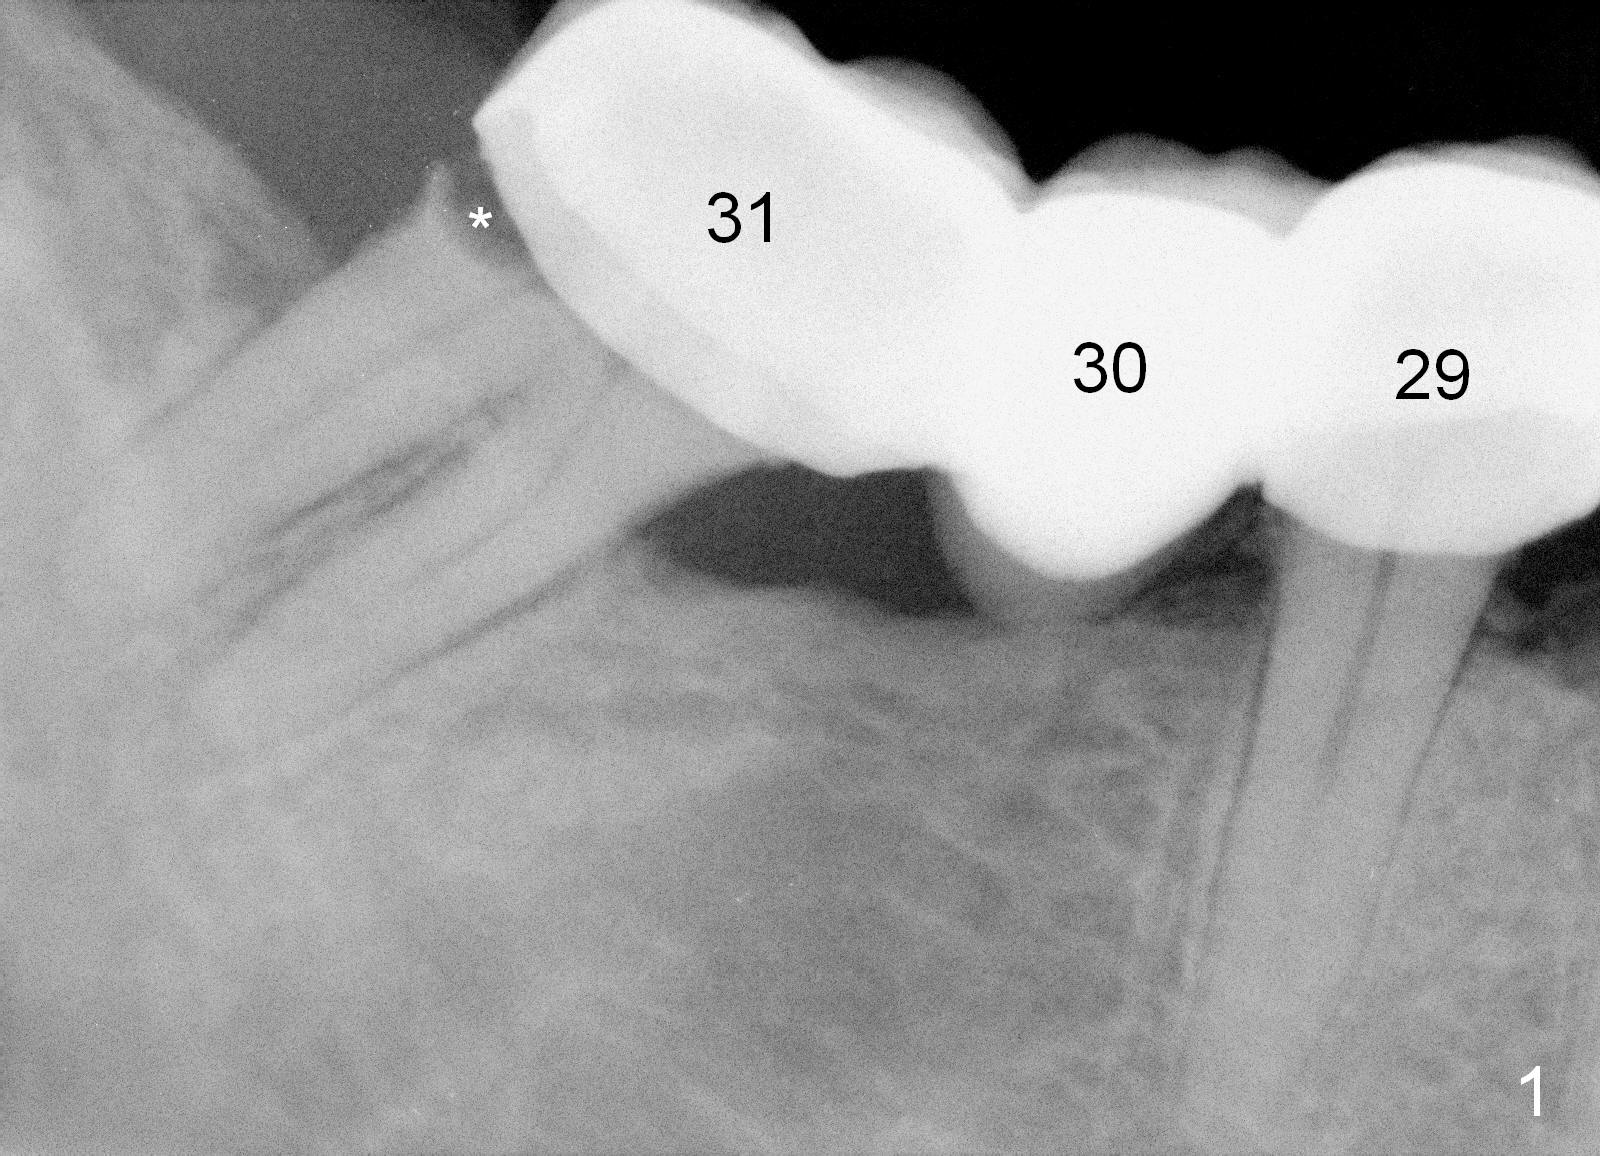

A 43-year-old man has a failed bridge (Fig.1: #29-31). The mesiodistal width of the pontic (#30) is pathologically narrow. When an implant is placed at the site, the osteotomy position should be moved distally, 5 mm from the distal surface of the tooth #29 (Fig.3), while the center of the osteotomy at the site of #31 should be 10 mm from the center of the osteotomy at the 1st molar.

Therefore, it is safer to place an implant coronal to the white arrowheads, i.e., 2 mm apical to the apex of the mesial socket (compare Fig.2,3).